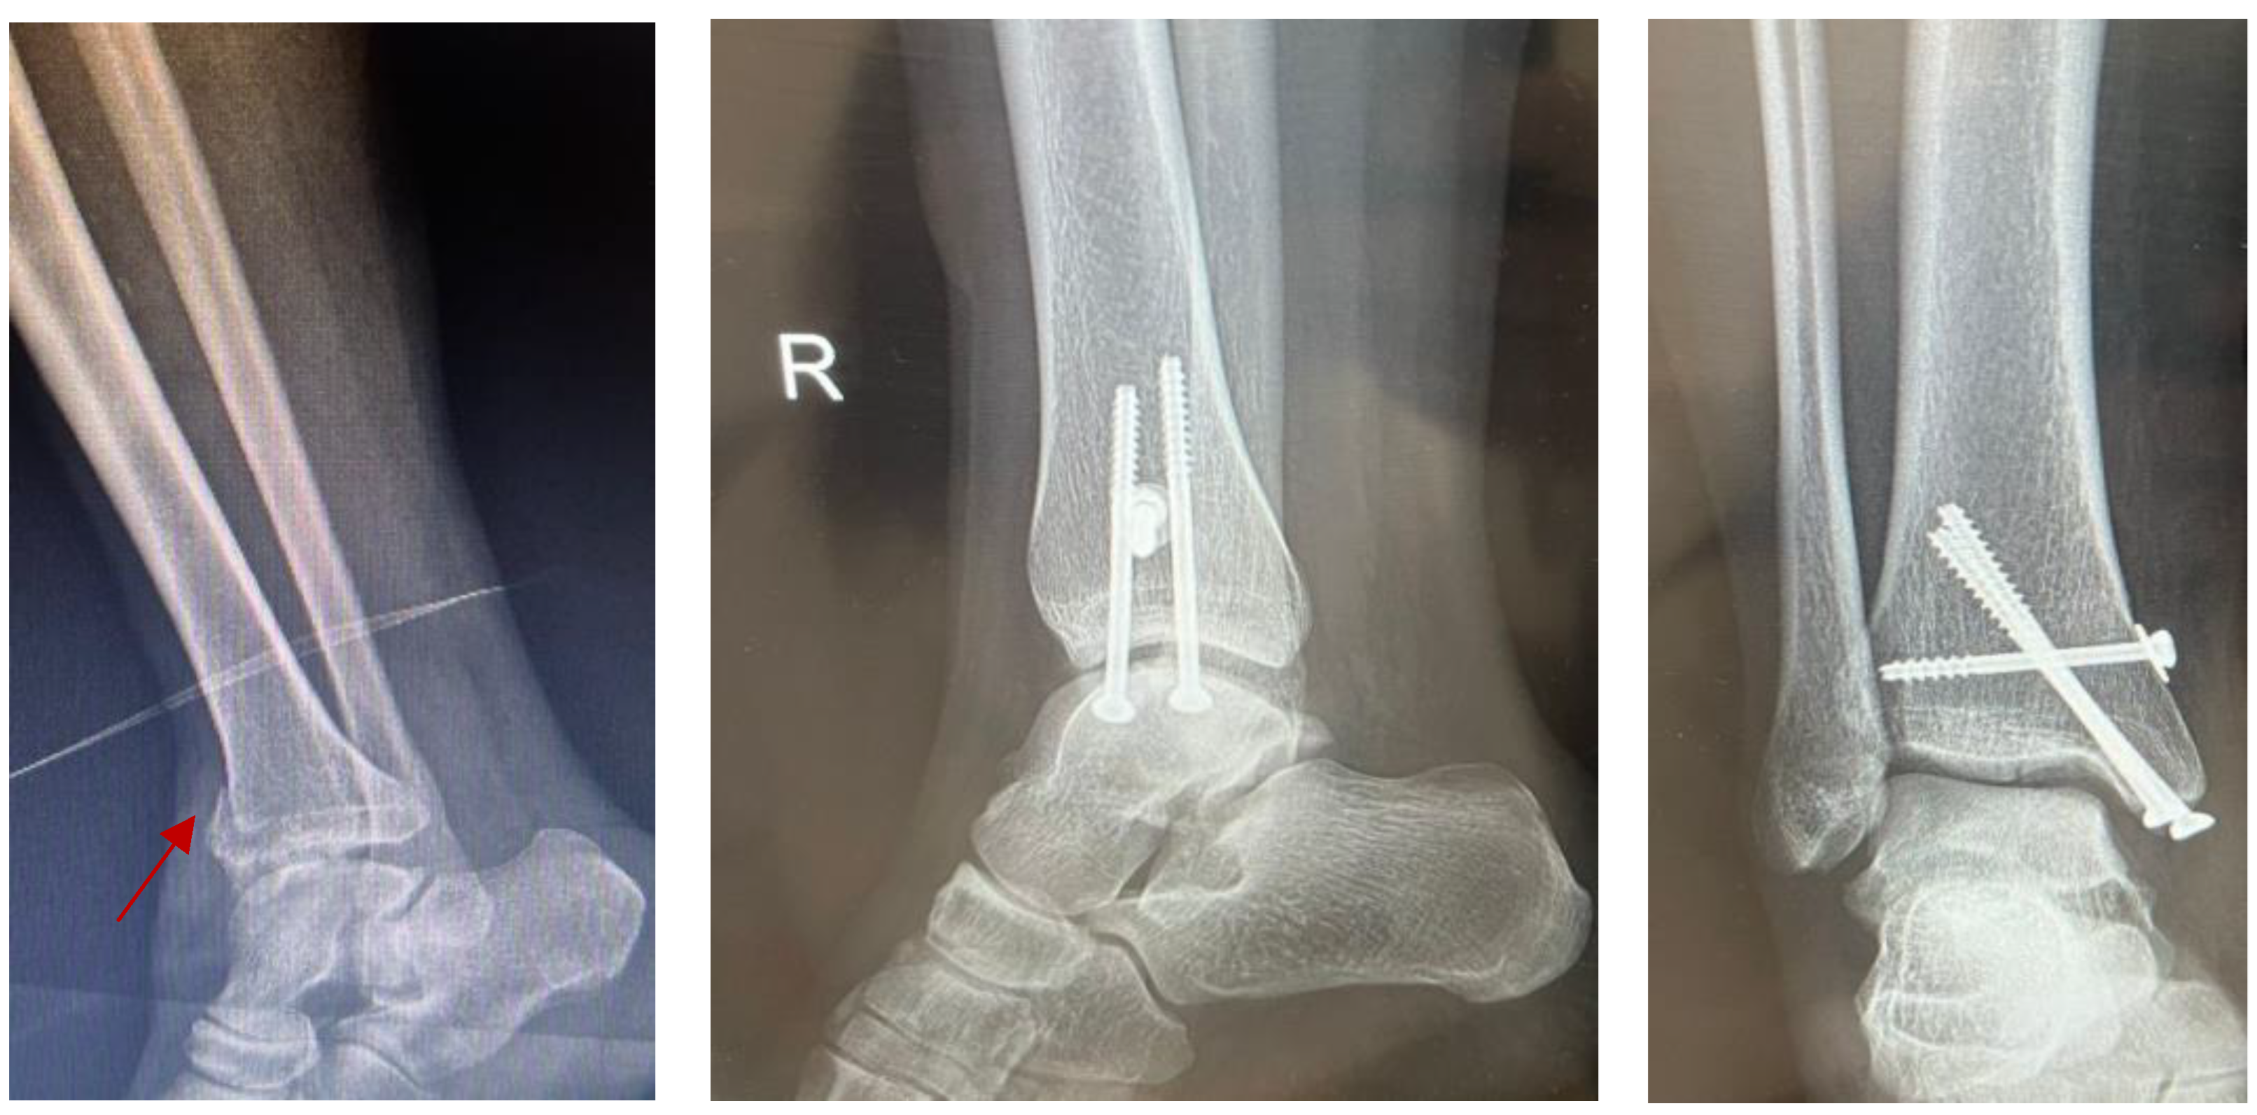

4.1.1. Surgical Management: Open Reduction and Internal Fixation (ORIF)

4.1.2. Minimally Invasive Surgery (MIS)

4.1.3. External Fixation and Arthroscopic Technique